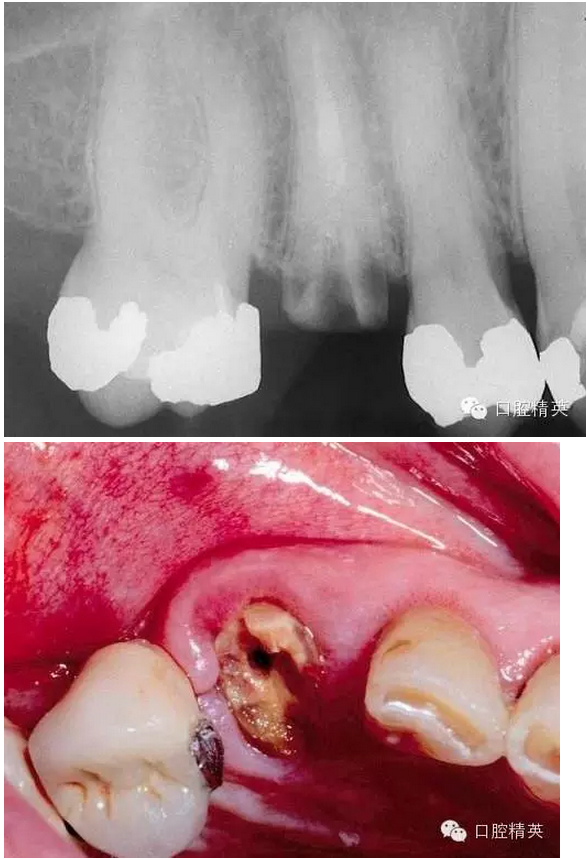

看看一個雙尖牙根的拔除 ,我常常對年輕的大夫說,我覺得難拔的不是下頜阻生智齒,而是有雙根的上頜雙尖牙,特別是一些正畸需要拔出的健康牙。

拔除后軟硬組織的創(chuàng)傷都很小。